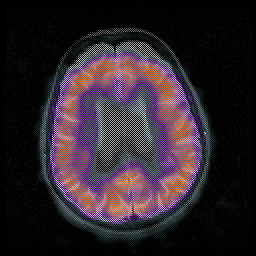

Huntington's Chorea, MR -- Slice #13